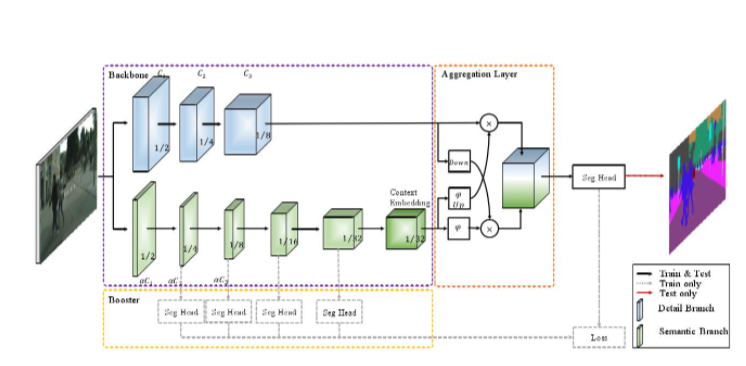

搭建训练全流程

模型->损失函数->优化器->超参数->train

模型:采用BiSeNetV2,因为这个模型很轻量,模型文件大概只有9.7MB左右。在部署的时候只有CPU的环境下运行,所以选用它。

损失函数:CrossEntropyLoss和DiceLoss的组合,7:3的比重。

优化器:采用优化器Momentum,学习率策略采用PolynomialDecay,初始化学习率为0.02

超参数:BatchSize为8.一共训练200轮

BiSeNetV2 结构图如下